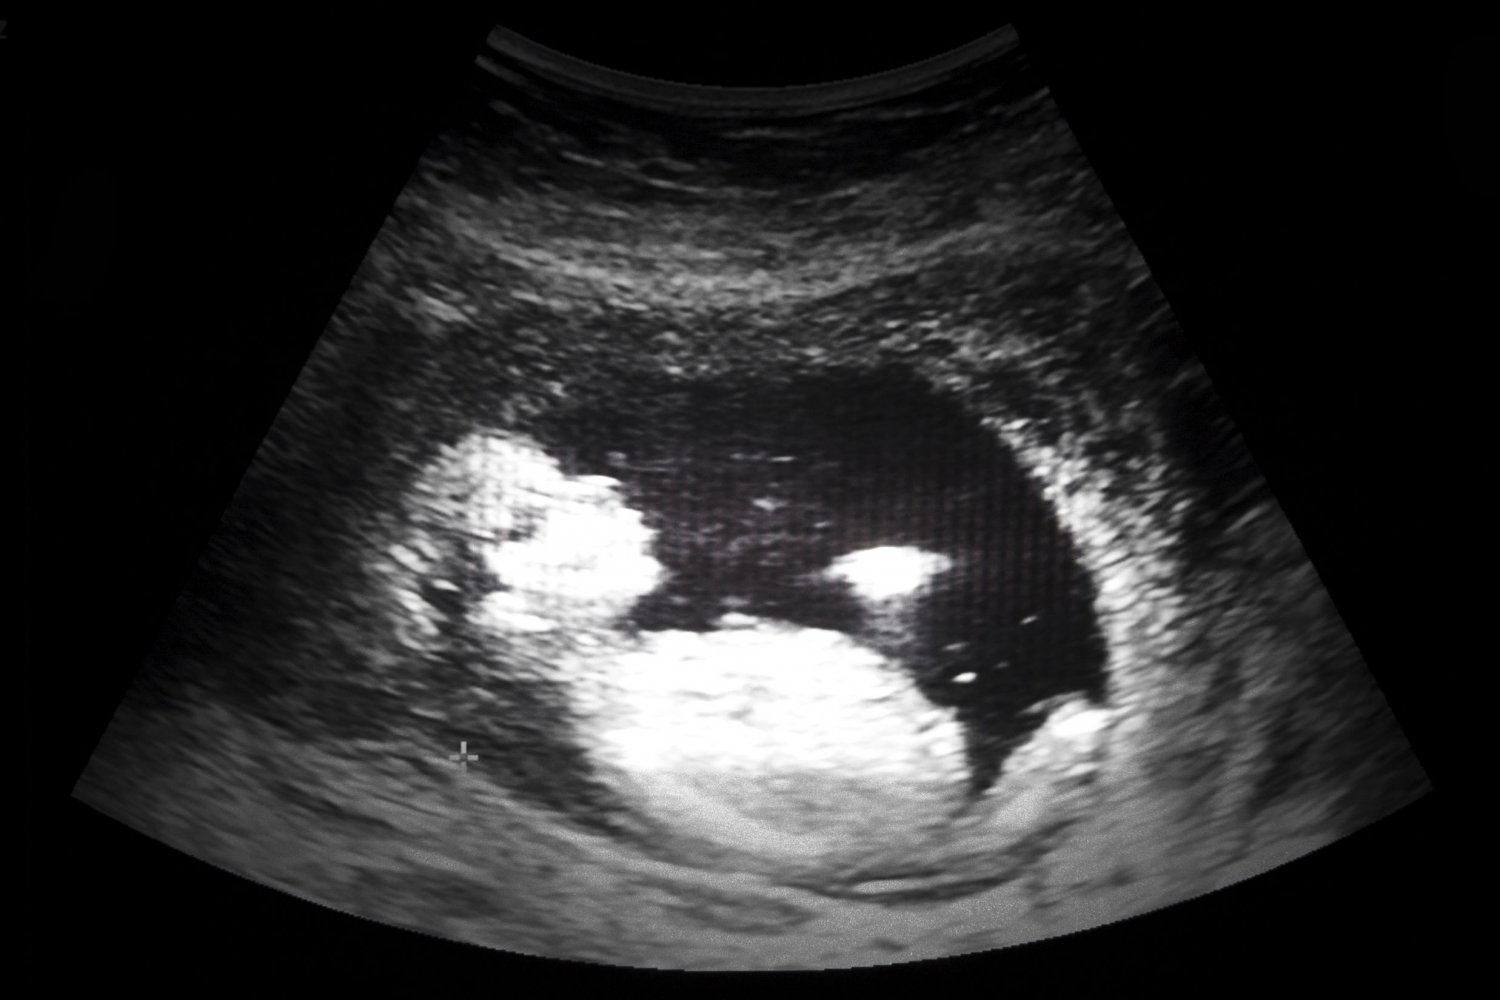

Płód w miarę jak rozwija się w łonie matki definiujemy inaczej. Najpierw jest zygotą, potem morulą, blastocystą …. itd. zarodkiem można go nazwać znacznie później. Z perspektywy jego rozwoju w jamie macicy , o płodzie mówimy, kiedy dochodzi do wyodrębnienia całej linii komórek z których będzie się on rozwijał i tworzy on w jamie owodni rozwijający się organizm , tj. w 5 tygodniu ciąży.

Fizjologicznie płód ma potencjalne szanse na przeżycie poza organizmem matki dopiero po 28 tygodniu ciąży. To tzw. kryterium zdolności przeżycia. W praktyce to ono jest najczęściej stosowane w określaniu granicy między płodem a człowiekiem. Do tego czasu mówienie o płodzie w łonie matki jako odrębnej i równorzędnie istocie ludzkiej jest absurdem.

Innym czasami stosowanym w tym rozróżnieniu kryterium jest uaktywnienie fal mózgowych podobnych jak w mózgu dorosłego człowieka. To moment, który przypada mniej więcej na 32 tydzień ciąży. Obecność fal mózgowych to czynnik świadczący o pracy układu nerwowego. . Ten sam zresztą, który stanowi główne kryterium przy definiowaniu śmierci klinicznej. To paradoksalne mówić o śmierci i narodzinach według tego samego schematu, jednak nie można zaprzeczyć, że obydwa zjawiska są w swoim charakterze podobne.